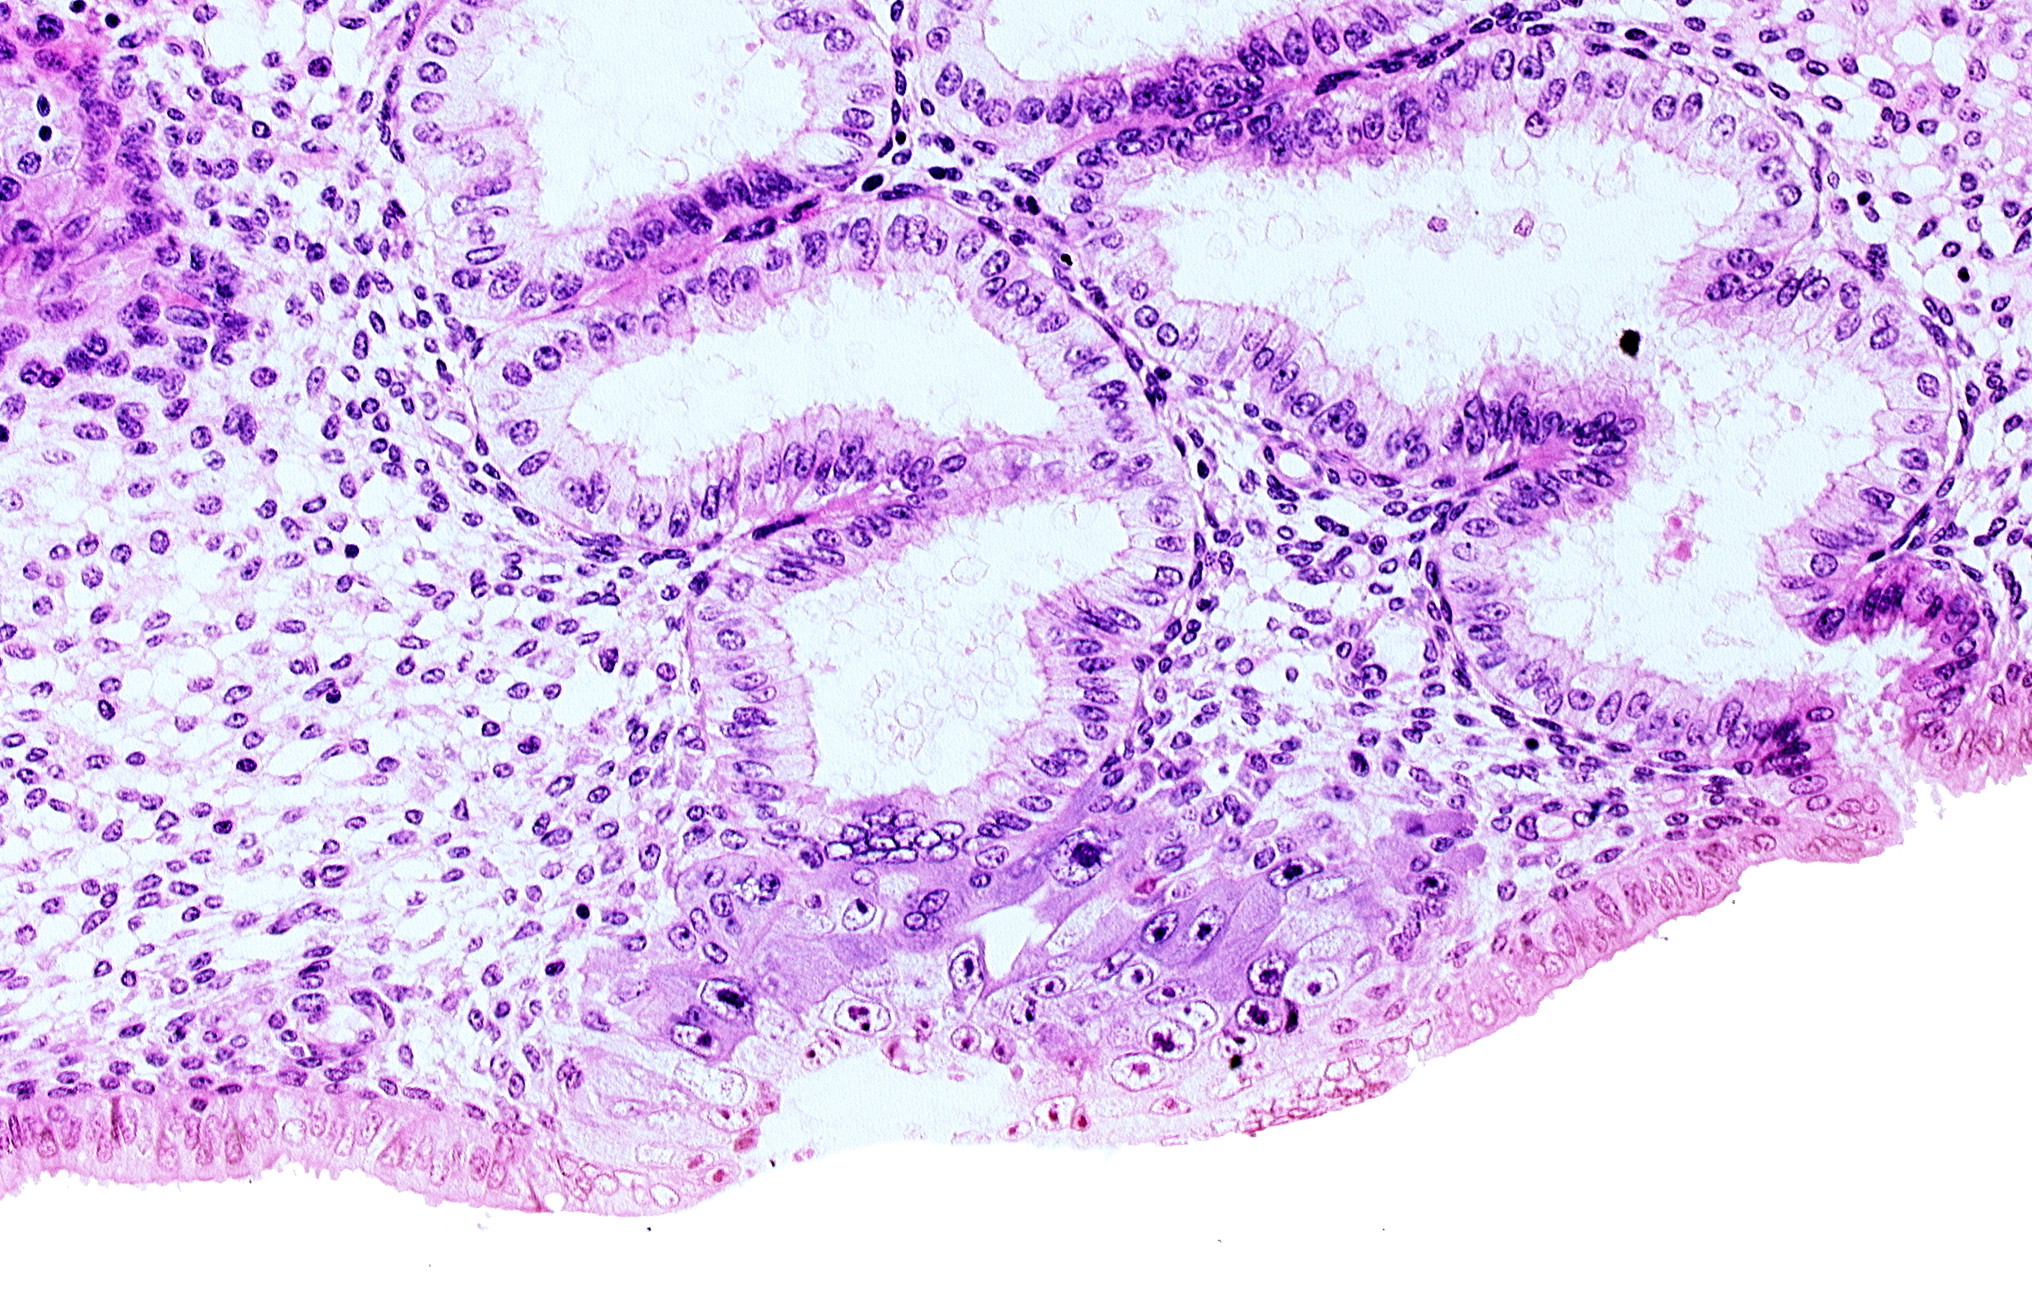

Carnegie Embryo #8020 | Location: 05-05-08

Keywords: blastocystic cavity (blastocoele), cytotrophoblast, endometrial epithelium, endometrial sinusoid, junction of endometrial gland and syncytiotrophoblast, membranous trophoblast at abembryonic pole, space(s) within syncytiotrophoblast